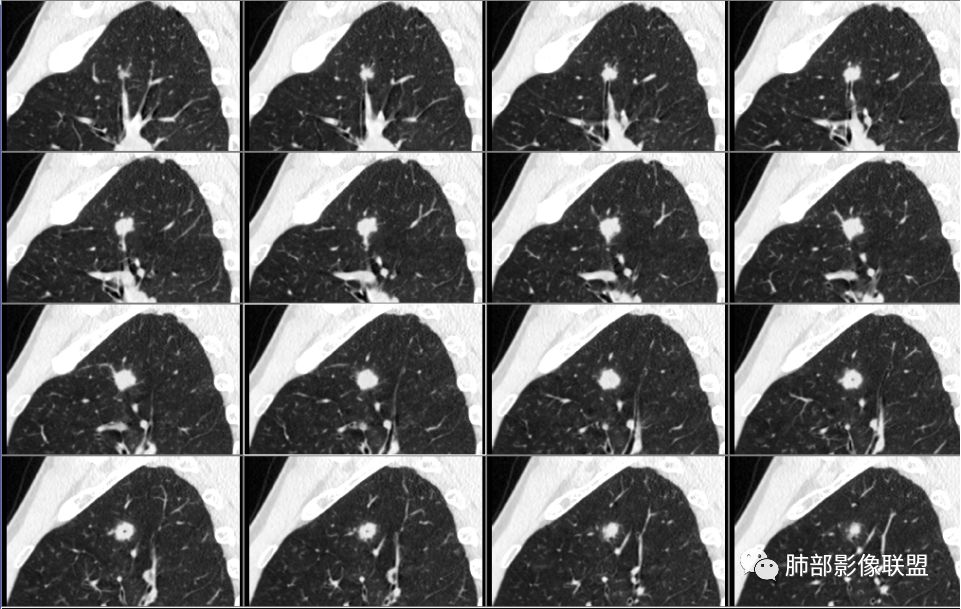

病例2肉瘤样癌的病理意见有些出乎预料,也充分说明病变及影像表现的复杂性。病灶小结节支气管截断、空泡、分叶、短毛刺、血管集束征等似乎均符合肺癌的影像特性。肺鳞癌及肉瘤样癌往往范围较小就可以出现坏死,但如果结节太小则很少能够在影像上观察到坏死区或空洞,没有增强扫描图像更是如此。